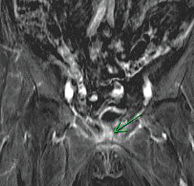

Sheela Madipelli, MD

Coarctation of the aorta (CoA) constitutes approximately 7% of all (CHDs). It is the most commonly missed CHD, and many cases are not diagnosed until adulthood, or death is incorrectly attributed to...